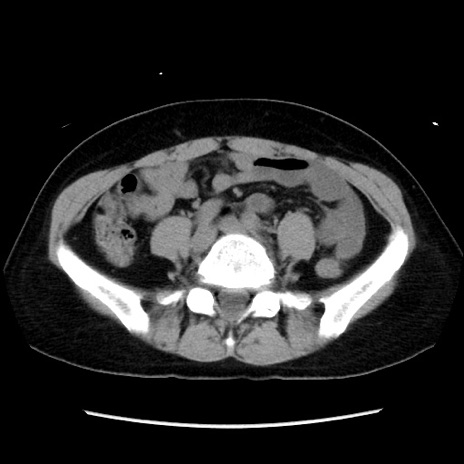

症例10(横断像)

【症例】 50歳代女性

【主訴】 腹痛

【現病歴】前日生レバーを食べた。今朝に排便あり。 昼前に突然発症の腹痛を生じ、当院救急外来を受診した。

【既往歴】 子宮筋腫にてで子宮全摘後

【身体所見】 意識清明、腹部:平坦、軟、下腹部やや左を中心に圧痛・反跳痛あり、筋性防御あり

【データ】WBC 7800、CRP 0.07